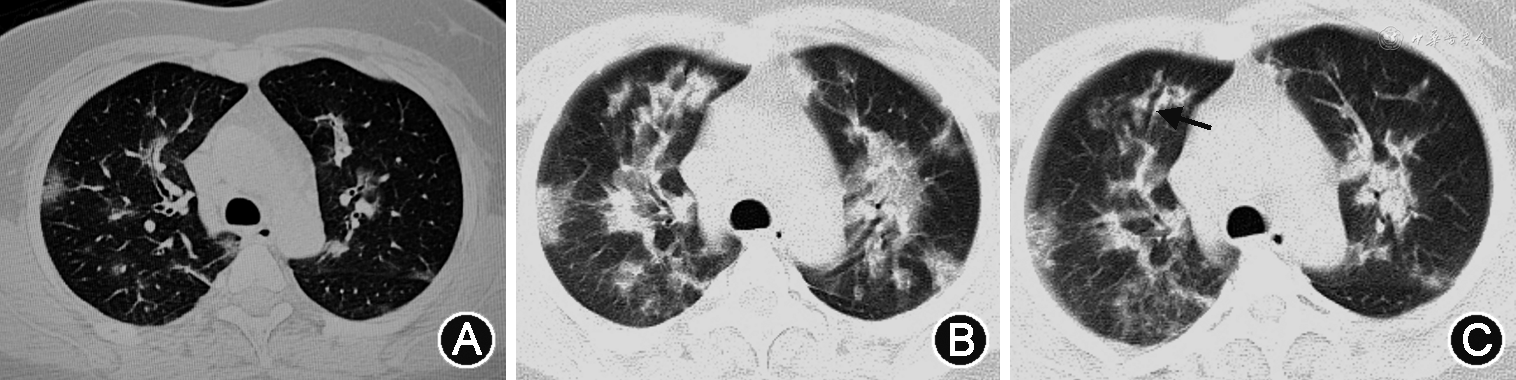

1. 重症病例:(1)X线:双肺受累多见,多发生在下肺[11, 12]。双肺纹理模糊,局限性或弥漫性分布的磨玻璃样改变及实变,部分可见弥漫性网状或结节状阴影。病程进展,病灶范围扩大,单侧病变可进展为双侧病变,单灶或多灶病变可进展为弥漫性病变,磨玻璃改变可融合为大片状实变[13]。可伴有胸腔积液[13]。合并肺气肿时,在病毒性肺炎基础上可见肺野透光度增强;合并细菌性肺炎时,表现为局灶性片状高密度影(图1)。(2)CT:单纯甲型H1N1流感重症肺炎病变常累及多个肺段及肺叶,病变可随机分布,但以双肺中下部周边为主[14, 15, 16, 17]。病变多表现为GGO和实变,或二者混合存在。磨玻璃阴影多位于周边,实变多靠近肺门,其内可见空气支气管征[18, 19, 20, 21](图1、2)。随病情进展,GGO会转化为实变,实变吸收也会转变成GGO。此外,还可见支气管血管束增粗、牵拉性支气管扩张等表现[16,22, 23](图3)。小叶间隔增厚、小叶中心结节等表现由于病情进展常常被掩盖,恢复期可见[24]。肺门及纵隔淋巴结肿大、胸腔积液和胸膜增厚等表现相对少见[25, 26]。肺栓塞亦可见,且发生风险较高[11,27]。可合并其他细菌性肺炎,进而形成合并性影像表现[12, 13,17]。治疗后恢复吸收阶段,病灶大多数可吸收,呈肺内广泛条索状、斑片状改变,甚至消失,部分病灶残留纤维瘢痕[22, 23]。

甲型H1N1流感重症肺炎进展快、吸收消散亦快。吸收往往从肺实变开始,表现为肺阴影变淡和密度不均,以及不同程度的纤维化改变[36](图5)。GGO及实变1周内出现,2周达到峰值,4周及以后吸收或消失[23]。纤维化在发病第1周即可出现,在发病第3周达到峰值,然后缓慢下降。对于病程较长的危重症患者,恢复吸收相对较慢[37](图5)。黎淑娟等[38]将甲型H1N1流感重症肺炎病变CT动态变化分成3种类型:先进展后吸收型、先吸收和进展并存后吸收型以及逐渐吸收型。

甲型H1N1流感重症肺炎患者的胸部影像变化不仅与疾病本身发展规律有关,还与治疗、是否合并其他病原体感染或基础疾病,以及患者年龄、体质等有关[12,25,29, 30,36]。